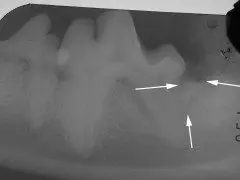

Surgical treatment of periodontal disease.

In some cases, deeper areas of periodontal disease with bone loss can be surgically treated to regenerate the bone, heal the void under the gum line and save important teeth. This form of treatment, termed “open root planing”, creates an environment for the normal supporting tissues of the tooth to regenerate.

Dental radiograph shows the graft material placed into the defect. The smaller, less important, adjacent molar has been extracted.